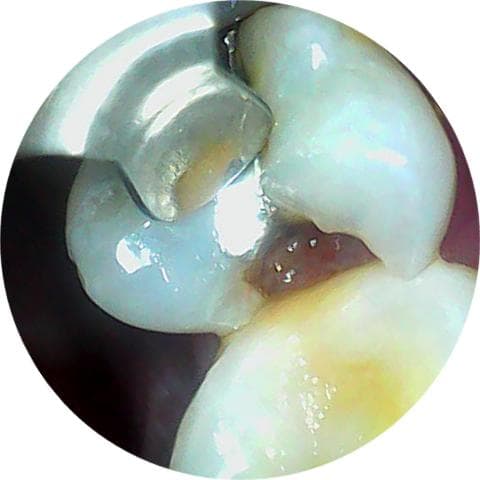

며칠 아프다가 안 아파져서 잊고 살았는데, 어떤 상태인지 궁금해서 카메라로 찍어봤더니 요래 됐네요;;

사진상으로도 충치가 상당히 진행된 상태 같습니다 .치료를 최대한 빨리 하시는게 좋을것같습니다.

이전의 아말감이 떨어져 나가고 내부로 충치가 생긴것으로 보입니다. 해당부위에는 이물질이 끼게 되어 충치가 더 생길수 있으며 치아가 파절될수 있기때문에 빠른시일내에 치료를 해주는것이 좋습니다.